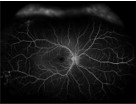

O exame tem como objetivo avaliar a circulação nos vasos sanguíneos da retina, é feito o uso de um corante chamado de fluoresceína sódica, injetado de maneira intravenosa no paciente, visando evidenciar os vasos sanguíneos da retina e defeitos retinianos.

É Indicado para pacientes com: Retinopatia diabética; Doenças oclusivas da retina, como obstrução da veia ou artéria retiniana;Outras doenças vasculares da retina; Doenças degenerativas, como DMRI e distrofias retinianas; Processos inflamatórios, como retinites, neurites, esclerite, posterior, entre outros; Tumores oculares, dentre outras alterações.